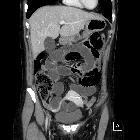

CT

Features are those of a pelvic small bowel closed-loop obstruction:

- small bowel dilatation

- double transition point in pelvic location, lateral to the uterus.

- pelvic free fluid